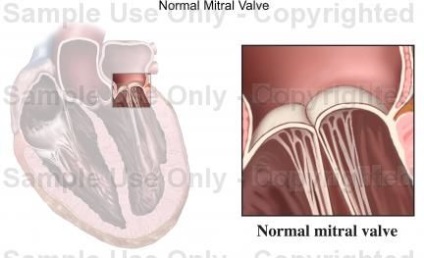

Néhány világosabban értelmezett illusztráció.

A bal oldalon - Peter Griffin másik fordított üdvözlete a norma ábrázolásában:

Itt látható a mitrális szelep működésének ciklusa (nyitott - zárt) - ismét a szelep szélén lévő probléma: